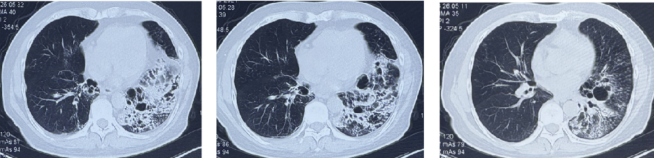

患者,男性,67岁,因“反复咳嗽咳痰40余年”就诊。患者既往于外院明确诊断为“支气管扩张症”,长期间断接受抗感染及止咳祛痰治疗,症状反复。近1月咳嗽、咳痰症状加重,痰液呈黄色,黏、不易咳出,无发热、胸痛、咯血、呼吸困难等其他不适。期间曾自行服用头孢地尼、西他沙星等药物,症状无明显缓解,遂至我院门诊就诊。听诊双肺可闻及湿啰音,左下肺明显;胸部高分辨CT检查(图1)提示:左肺广泛囊状及柱状支气管扩张,以下叶为著。左肺多发斑片状实变影及结节影(部分伴小空洞形成)。

图1 患者胸部CT